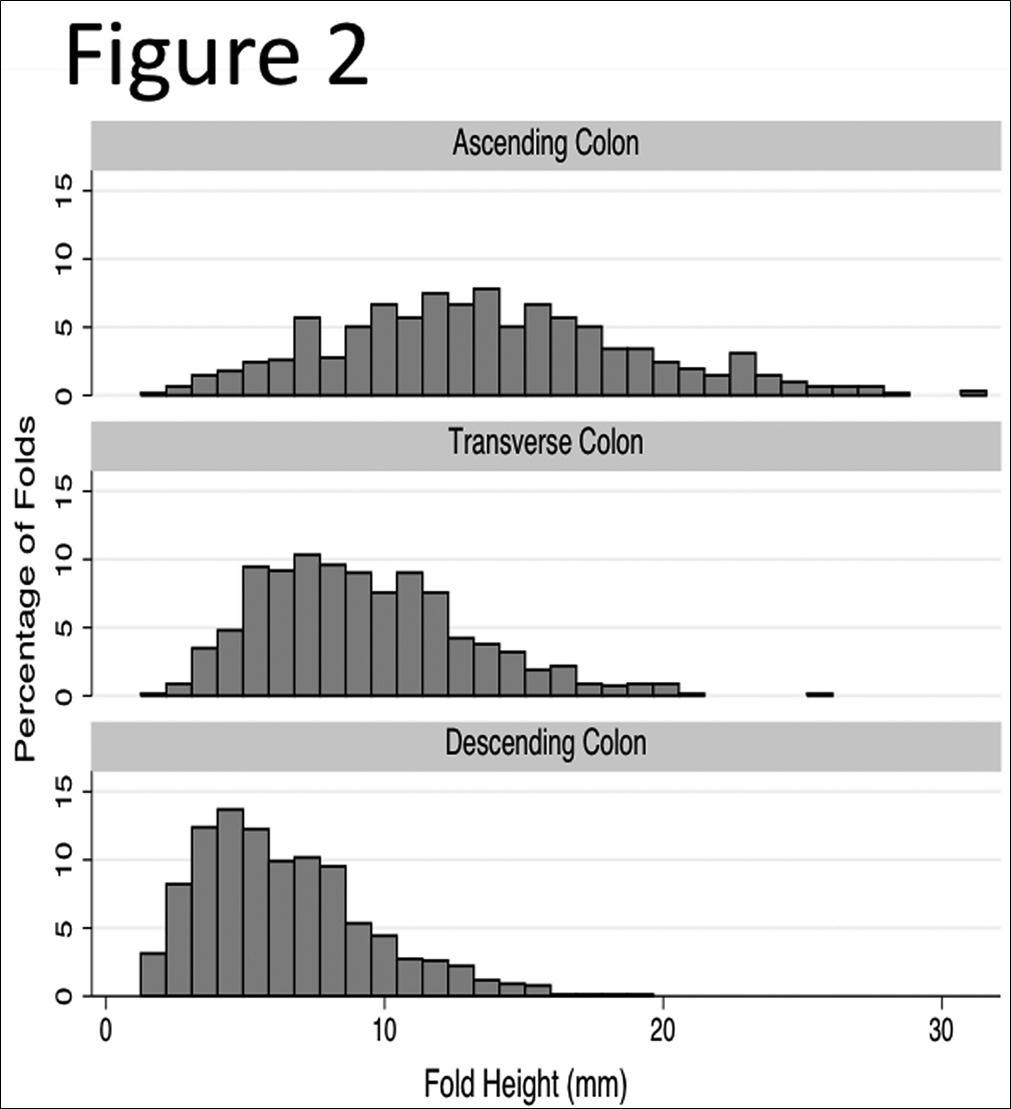

We measured haustral fold heights (HFHs) of the colon in 50 patients. The mean age of the study patients was 60.5 ± 6.8 years. Thirty-five of the patients were male and 15 were female. A total of 2079 colonic folds were measured: 625 in the ascending colon (including the cecum), 687 in the transverse colon, and 767 in the descending colon. The mean number of folds measured per segment was 6.87 ± 2.11. This minimum number of five fold pairs was within one standard deviation of the mean number of fold pairs measured per segment (6.87 ± 2.11). Figure 2 shows histograms of the distribution of colon fold measurements in each of the three colonic segments. Mean haustral fold heights in the ascending colon (including the cecum) (14.62 ± 5.47 mm) were significantly taller than in the transverse (9.49 ± 3.65 mm, P<0.0001) or descending colon (6.53 ± 3.12 mm, P<0.0001) (Table 1). Folds in the transverse colon were also significantly taller than in the descending colon (P<0.0001). The ascending colon (including the cecum) folds were 7.60mm (95% CI: 7.09-8.11 mm) and 4.61mm (95% CI: 4.12-5.11 mm) taller than the descending or transverse haustral folds, respectively(Table 2).

Figure 2.Distribution of Haustral Fold Heights in the Ascending, Transverse and Descnding Colon. Y-axis shows percentages of height in each colonic segment, respectively.